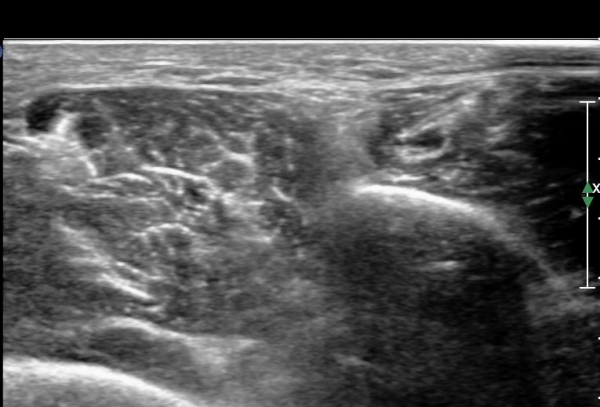

¾Æ·§´Ù¸® ¿ÜÃø Ⱦ´Ü¸é°Ë»ç¿¡¼ Àåºñ°ñ±Ù°ú ¹ß°¡¶ô½ÅÀü±Ù »çÀÌ¿¡¼ õºñ°ñ½Å°æÀÌ Á¤»óÀûÀ¸·Î °üÂûµÈ´Ù(»çÁø 1, , 2, 3, 4, 5).

¾ÕÂÊ ¸»´Ü °æ°ñºñ°ñ°üÀý ¾à 5cm ±ÙÀ§ºÎ Ⱦ´Ü몀°Ë»ç ½Ã õºñ°ñ½Å°æ Àü¸é¿¡ Àú¿¡ÄÚ ³¶Á¾¿¡ ÀÇÇÑ ½Å°æ ¾Ð¹ÚÀÌ °üÂûµÈ´Ù(ÀÌ °üÂûµÈ´Ù(»çÁø 6, 7).

¸»´ÜÀ¸·Î °¥ ¼ö ·Ï ³¶Á¾ÀÌ Ä¿Áø°í õºñ°ñ½Å°æ ¾Ð¹ÚÀº ½ÉÇØÁø´Ù(»çÁø 8).

³¶Á¾À» Á¾´Ü¸éÀ¸·Î °üÂûÇÏ´Ï ³¶Á¾ÀÌ ¸»´Ü °æ°ñºñ°ñ°üÀý¿¡¼ À¯·¡µÊÀÌ È®ÀεȴÙ(»çÁø 9).